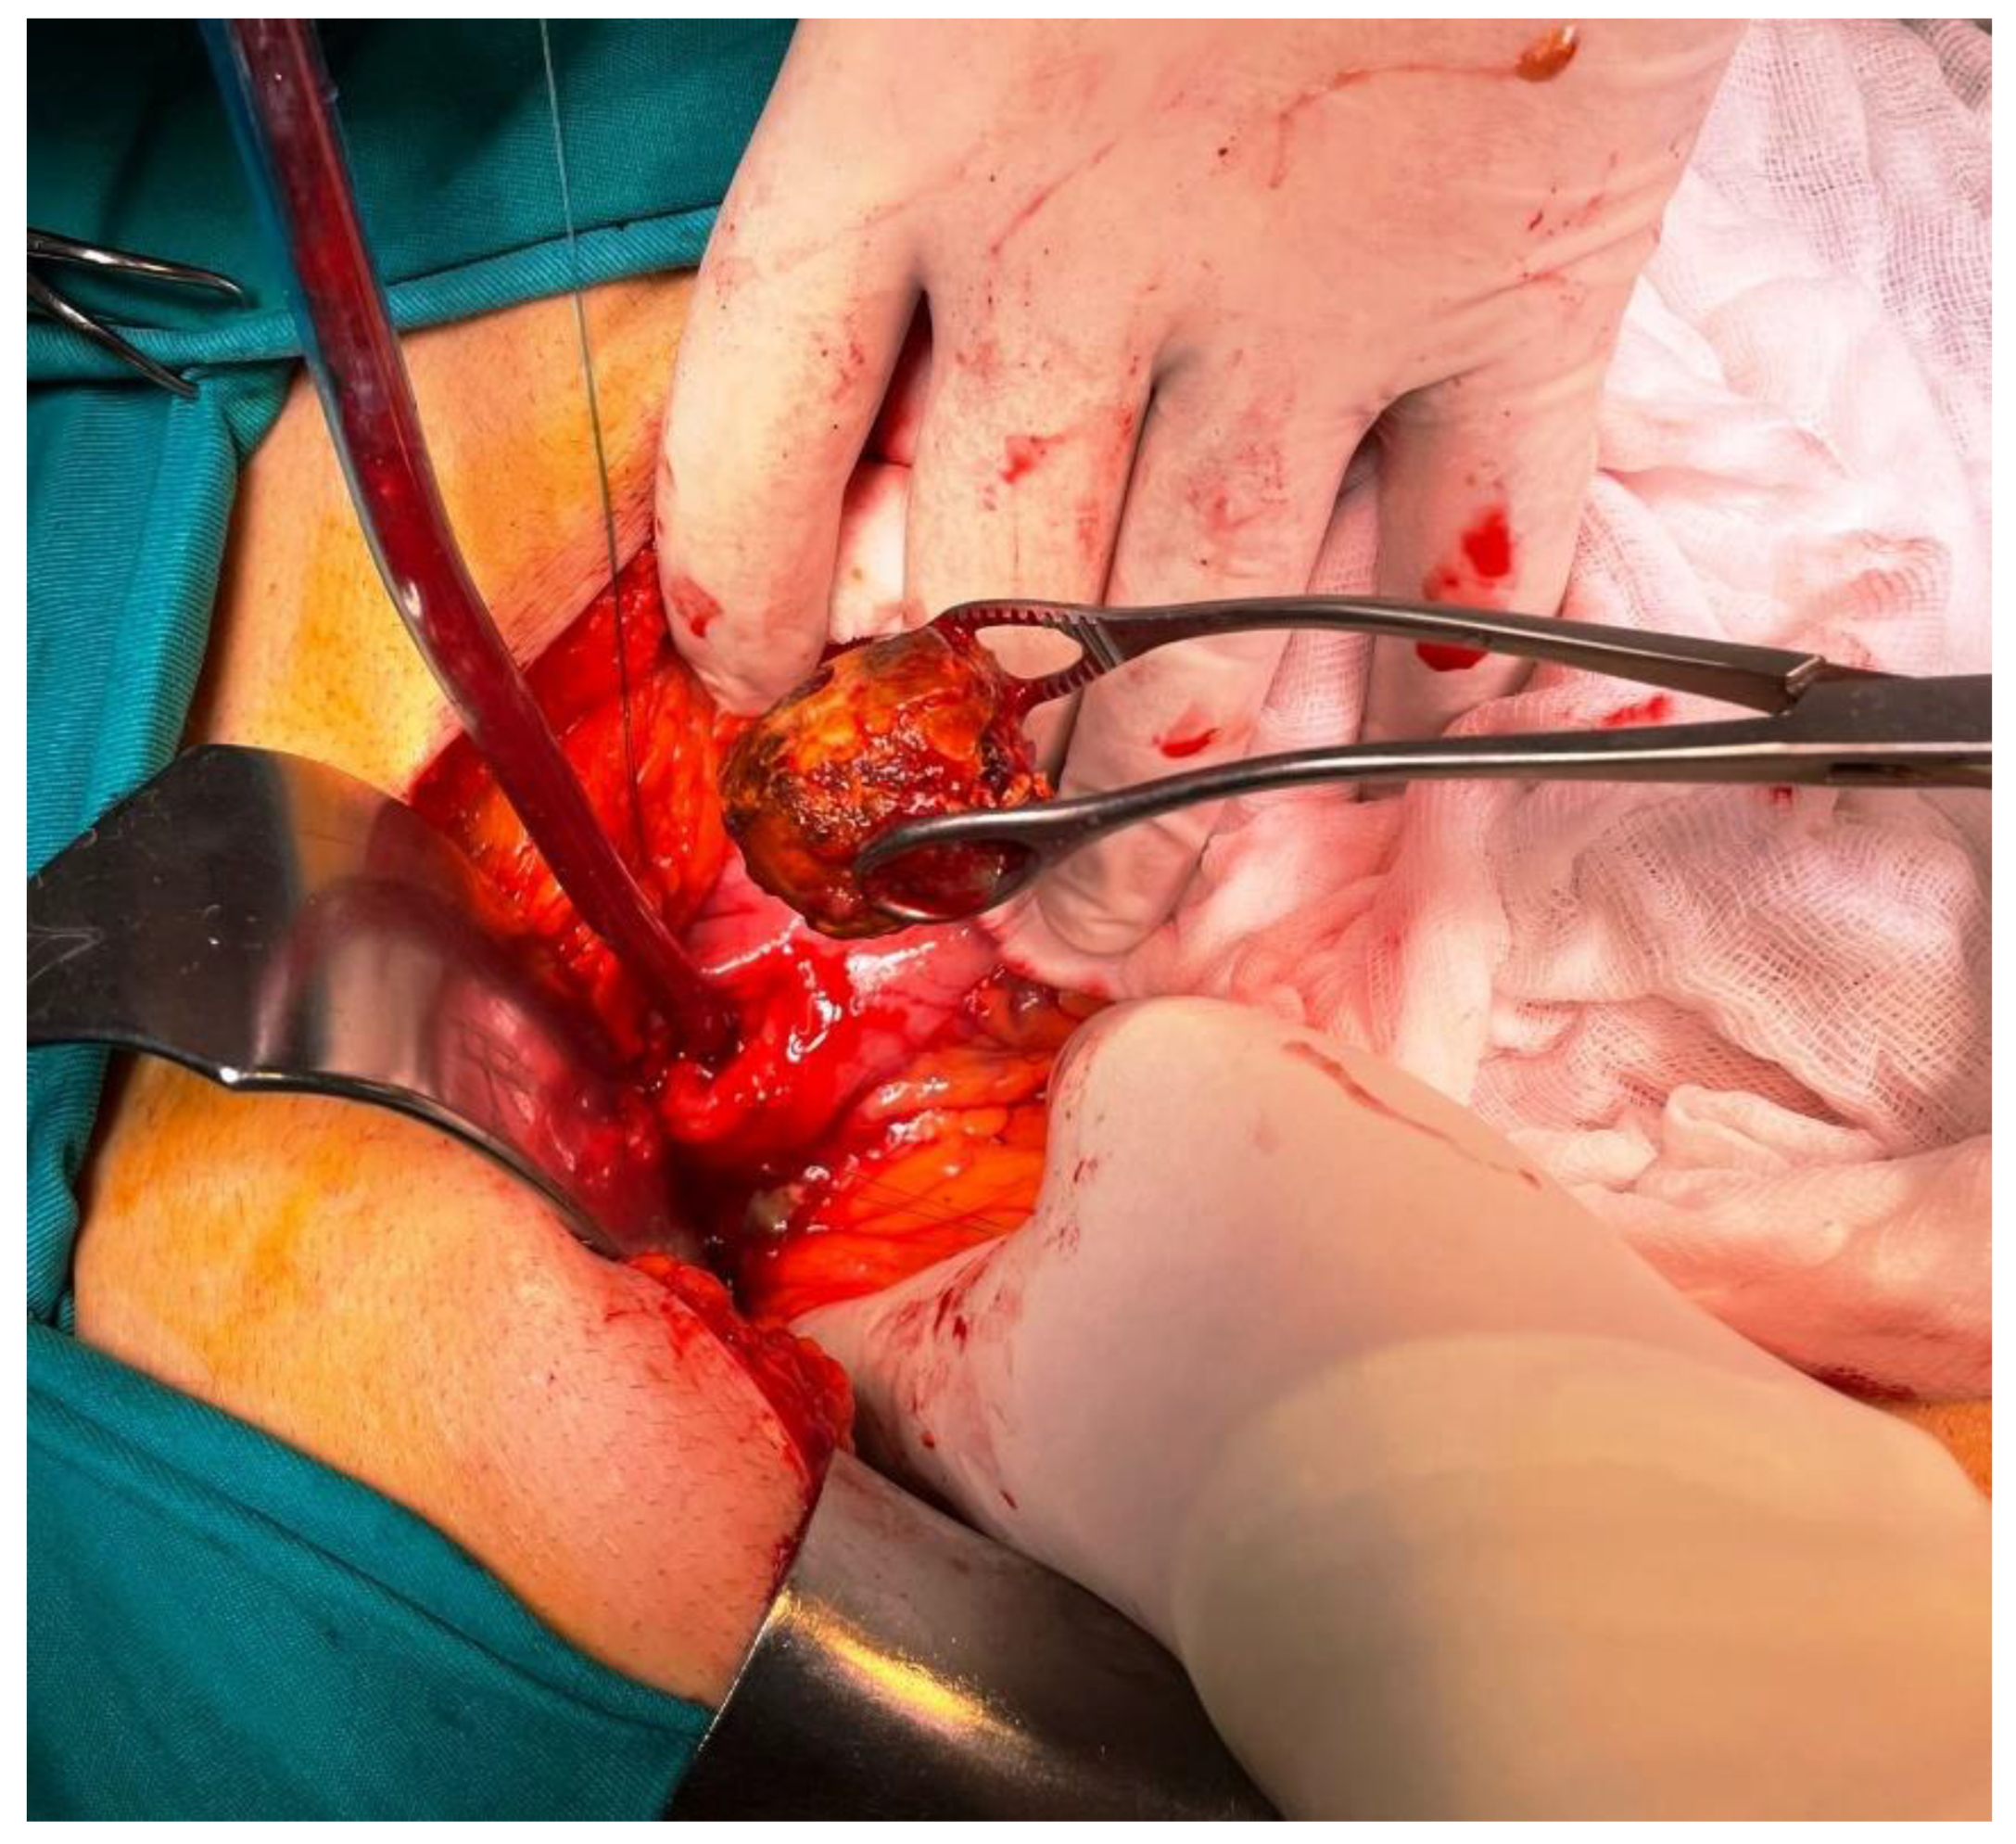

Figure 7, Figure 8 and Figure 9 Patient immediately have been treated by open surgery including gallstone extraction, gastrotomy, duodenal suture and cholecystectomy (Figures 7,8,9). Both parenteral nutrition and antibiotics were introduced during the postoperative period so patient was discharged after 7 days. Enterotomy or gastrotomy with or without cholecystectomy and fistula repair remains the treatment of choice. It has high success rate, with acceptable surgical morbidity and mortality [11]. It is still a matter of debate whether cholecystectomy and repair of the fistula should be performed, due to spontaneous closure of fistulas in some cases [9,12,13]

Figure 7. Intraoperative findings.

Preprints 107205 g007

Figure 8. Intraoperative findings.

Preprints 107205 g008

Figure 9. Intraoperative findings.

Preprints 107205 g009